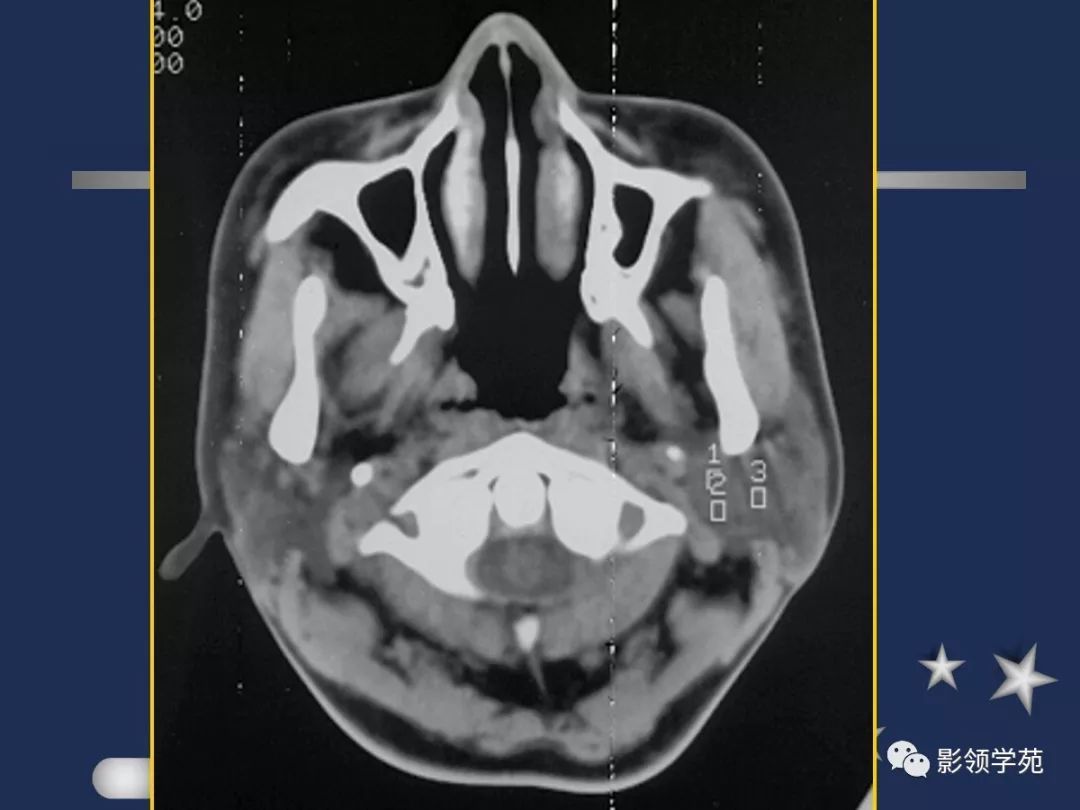

- 位于下颌骨后,胸锁乳突肌前,上致颅底,位于乳突尖和颞颌关节之间,下至下颌角,是茎突前咽旁间隙重要器官

- 腮腺是脂肪性腺体,CT呈低密度

- 腮腺内血管显示清楚